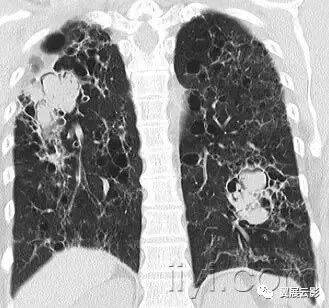

四十六、全腺泡性肺气肿

病理:全腺泡性肺气肿累及腺泡全部,累及次级肺小叶相对均一。主要累及下叶,该型肺气肿与抗胰蛋白酶缺乏有关。

CT:全腺泡性肺气肿表现为肺实质密度广泛性减低,病变肺的血管直径减小,严重的全腺泡性肺气肿可以与小叶中心性肺气肿并存并融合。乏特征性密度减低影与狭窄性闭塞性细支气管炎难以鉴别。与全小叶性肺气肿是同义词。